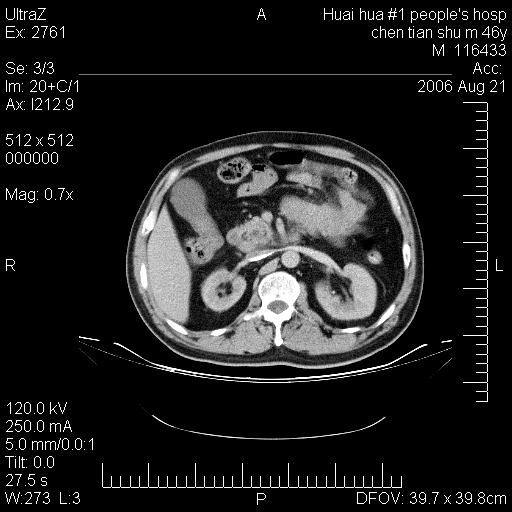

患者,男,46y。腹痛2月,消瘦。

十二指肠水平段占位,考虑间质瘤或平滑肌瘤。

肿块较大,腹膜后占位,境界欠清,周边脂肪密度较高呈条状影,有没有脂肪肉瘤可能,

缺少完整的三期图像。考虑肠系膜脂膜炎mp(肿块型)。

鉴别:间质瘤(这么大而无囊变不可思议)、平滑肌瘤/肉瘤、淋巴瘤、类癌,脂肪类肿瘤、转移瘤等。

十二指肠水平段占位,考虑间质瘤。

首先考虑小肠间质瘤。

十二指肠水平段软组织密度占位,考虑间质瘤可能性大。

腹膜后占位,境界欠清,考虑来源于十二指肠病变,间质瘤或平滑肌肉瘤可能性大。建议活检。

手术病理结果:原发性小肠恶性淋巴瘤(primary gastrointestinal lymphoma,pgil)是原发于胃肠的淋巴网织系统的恶性肿瘤,在结外淋巴瘤中居第一位,该病少见,临床无特异性,诊断困难,术前主要依靠影像学诊断。胃肠道本身具有较丰富的淋巴组织,因而胃肠原发性淋巴瘤是结外淋巴瘤最常见的部位,文献报道约占胃肠道恶性肿瘤的1%~4%,其中胃约占50%~70%,小肠约占35%~70%,结肠约占4%~6%。影像检查在pgil的诊断及分期中有重要的作用,ct是很有价值的检查方法。

胃肠淋巴瘤病理特点:胃肠道原发性淋巴瘤起源于胃肠壁固有层和黏膜下层的淋巴组织即胃肠粘膜相关淋巴组织(malt),多为粘膜相关淋巴瘤。病理上通常为非霍奇金淋巴瘤,且决大多数来源于b淋巴细胞,很少见于霍奇金淋巴瘤。胃肠原发淋巴瘤比胃肠道癌的发病率要低的多,最常见于胃,其病因可能跟幽门螺杆菌感染有关。幽门螺杆菌能引起胃粘膜损害,引起炎性及免疫反应,淋巴细胞聚集并形成滤泡,可影响胃的正常生理功能,导致胃淋巴瘤的发生。单纯性小肠淋巴瘤是常见好发于回盲末端,受累的肠段较长,可单发、多发,甚至累及整个小肠。原发性大肠淋巴瘤罕见,以直肠和盲肠最多见。病变大体观可表现为胃肠腔内外的肿块,也可表现为从黏膜下到浆膜面肠壁的纵向浸润,并且常常伴有肠系膜淋巴结肿大。任何情况下,肿瘤几乎总是导致一定程度的肠壁增厚,可对称或不对称,病变与正常组织间常无明确分界,肠腔可狭窄、正常或动脉瘤样扩张,后者主要是肿瘤在肠壁内浸润,破坏肠壁内植物神经丛所致。以上改变成为ct检测病变的病理基础。

肠道淋巴瘤的ct表现分为4类

1) 壁内浸润型, (2)多发结节型, (3)肠系膜受累伴腔外肿块型(本型就是),(4)肿块型。